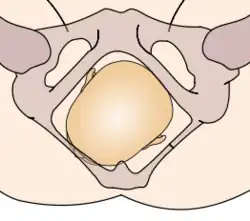

The vertex presentations are further classified according to the position of the occiput, both right, left, or transverse and anterior or posterior:

- Left Occipito-Anterior (LOA), Left Occipito-Posterior (LOP), Left Occipito-Transverse (LOT)

- Right Occipito-Anterior (ROA), Right Occipito-Posterior (ROP), Right Occipito-Transverse (ROT)

The occipito-anterior position is ideal for birth; it means that the baby is lined up so as to fit through the pelvis as easily as possible. The baby is head down, facing the spine, with their back anterior. In this position, the baby's chin is tucked onto their chest, so that the smallest part of their head will be applied to the cervix first. The position is usually "Left Occiput Anterior", or LOA. Occasionally, the baby may be "Right Occiput Anterior", or ROA.[5]